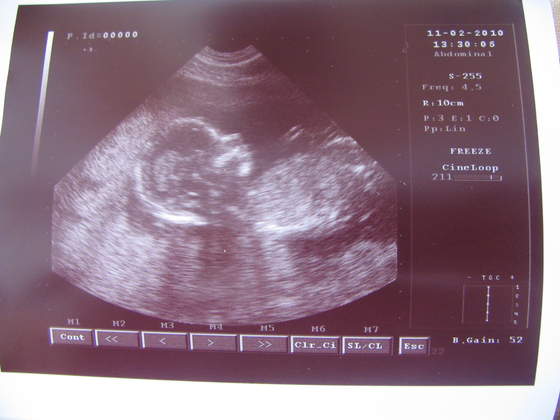

Dziewczyny, oto mój "Facet", wg wczorajszego USG

Zdjęcia, mam nadzieję, wyraźne... Skaner mi się popsuł, pozostało mi tylko zrobić "zdjęcie ze zdjęcia" :-)

lekarz powiedział, że na 100% to chłopczyk?No rewelacja!!!!!!!!!!!!!!!

Boski ten Twój facet,lekarz powiedział, że na 100% to chłopczyk?

Powiedziałam, że oczywiście. A on powiedział, że chlopak